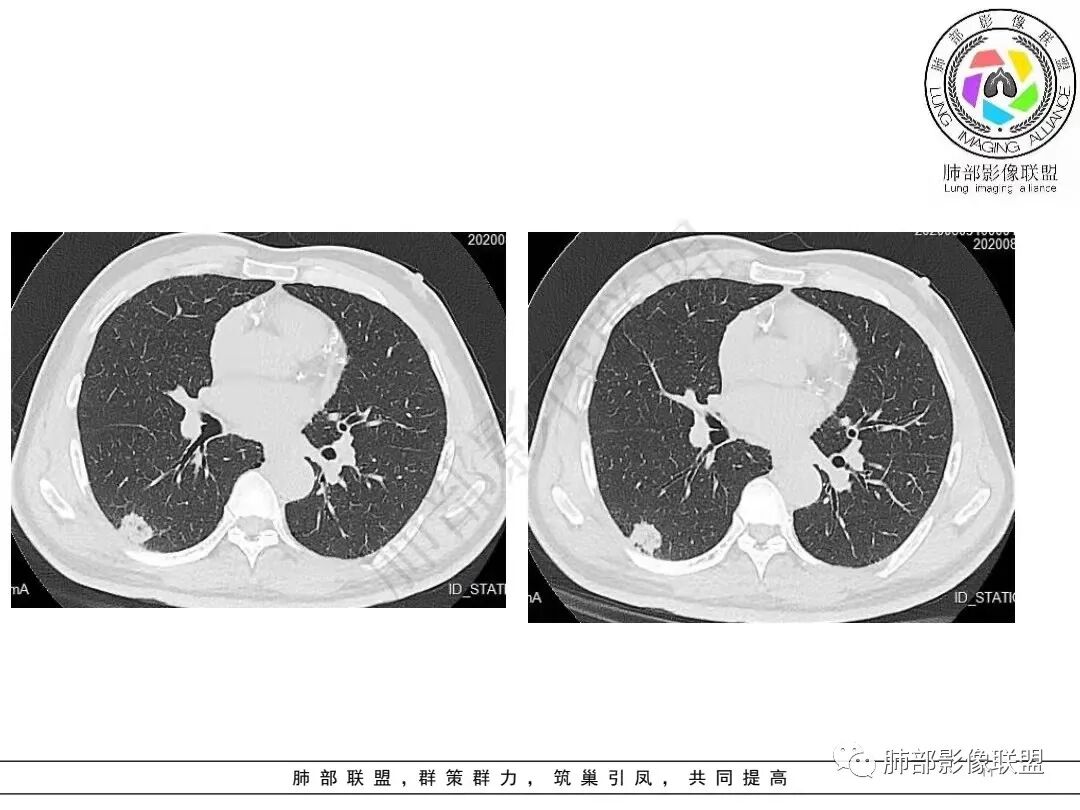

2.病例二:30岁女性,发现病灶6个月前有咳嗽咳痰及治疗史,肿瘤标志物阴性。左肺下叶胸膜下结节影,整体较膨隆,局部边缘较平直,可见毛刺,同样可见磨玻璃密度区,病灶内可见空泡征,周围可见细小毛刺及多发棘突影,同样外围病灶支气管情况难以判断。邻近肺组织内可见多发微小结节影。病灶张力不高,未见分叶及胸膜牵拉,由于纵隔窗图像太少,不宜判断胸膜下脂肪间隙有无受累,可疑胸膜下有微量积液。

综合分析:两份病例都是位于胸膜下的孤立结节,同样具有锯齿状边缘,有细毛刺、空泡。病例一老年男性+CEA显著升高,常规恶性病变肯定是要考虑;至于病例二青年女性,肿瘤标志物阴性,在未见非常典型恶性征象情况下,临床通常会优先选择炎性病灶进行处置,病灶持续存在,复查无变化或出现进展,则应想到新生物可能,而选择穿刺或其他进一步检查。